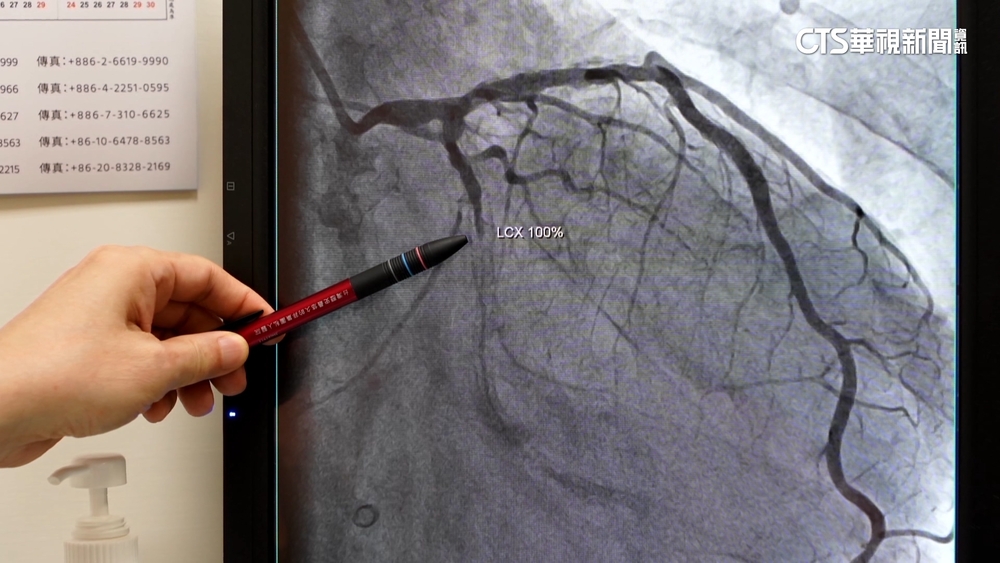

- 心血管疾病長年位居國人死因第二 醫:除控制三高 必要時應做心導管檢查2023/02/16